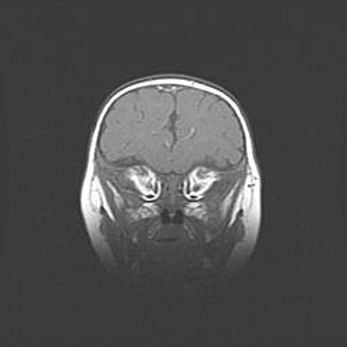

Множественные кисты обоих полушарий головного мозга, наибольшая из них в правой затылочной области. Ассиметричная атрофическая гидроцефалия.

Возраст: 7 месяцев

Вес: 5660 г

Пол: мужской

Окружность головы: 41,5 см

Срок гестации: 28-29 недель

Кисты головного мозга развиваются в результате многоочаговых некрозов вещества мозга и возникают вследствие перенесенной перинатальной инфекции, менингитов, энцефалитов, асфиксии, родовой травмы, расстройств мозгового кровообращения различного генеза. Образованию кист в веществе головного мозга плодов и новорожденных способствуют такие факторы, как высокое содержание в нем воды, недостаточная (или отсутствие) миелинизация и слабая астроглиальная реакция на повреждение.

Кисты могут сочетаться с гидроцефалией и другими поражениями головного мозга.